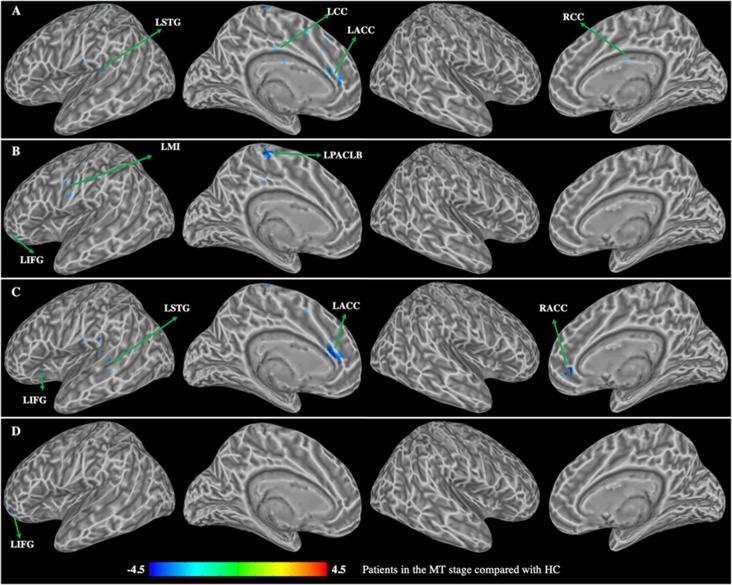

Several studies have demonstrated through resting-state functional magnetic resonance imaging (fMRI) that functional connectivity changes are important in the recovery from Bell's palsy (BP); however, these studies have only focused on the cortico-cortical connectivity. It is unclear how corticostriatal connectivity relates to the recovery process of patients with BP. In the present study, we evaluated the relationship between longitudinal changes of caudate-based functional connectivity and longitudinal changes of facial performance in patients with intractable BP. Twenty-one patients with intractable BP underwent resting-state fMRI as well as facial behavioral assessments prior to treatment (PT) and at the middle stage of treatment (MT); and 21 age- and sex-matched healthy controls (HC) were recruited and received the same protocol. The caudate was divided into dorsal and ventral sub-regions and separate functional connectivity was calculated. Compared with HC, patients with intractable BP at the PT stage showed decreased functional connectivity of both the dorsal and ventral caudate mainly distributed in the somatosensory network, including the bilateral precentral gyrus (MI), left postcentral gyrus, media frontal gyrus, and superior temporal gyrus (STG). Alternatively, patients in the MT stage showed decreased functional connectivity primarily distributed in the executive network and somatosensory network, including the bilateral cingulate cortex (CC), left anterior cingulate cortex (LACC), inferior prefrontal gyrus (IFG), MI, STG, and paracentral lobe. The longitudinal changes in functional connectivity of both the dorsal and ventral caudate were mainly observed in the executive network, including the right ACC, left CC, and IFG. Functional connectivity changes in the right ACC and left IFG were significantly correlated with changes in facial behavioral performance. These findings indicated that corticostriatal connectivity changes are associated with recovery from BP.

多项研究通过静息态功能磁共振成像(fMRI)表明,功能连接性变化在贝尔麻痹(BP)恢复过程中很重要;然而,这些研究仅关注皮质 - 皮质连接性。目前尚不清楚皮质 - 纹状体连接性与BP患者的恢复过程有何关系。在本研究中,我们评估了难治性BP患者基于尾状核的功能连接性纵向变化与面部功能纵向变化之间的关系。21例难治性BP患者在治疗前(PT)和治疗中期(MT)接受了静息态fMRI以及面部行为评估;并招募了21名年龄和性别匹配的健康对照者(HC),他们接受相同的检查方案。将尾状核分为背侧和腹侧子区域,并计算各自的功能连接性。与HC相比,难治性BP患者在PT阶段表现出背侧和腹侧尾状核的功能连接性降低,主要分布在体感网络,包括双侧中央前回(MI)、左侧中央后回、额中回和颞上回(STG)。另外,MT阶段的患者表现出功能连接性降低,主要分布在执行网络和体感网络,包括双侧扣带回皮质(CC)、左侧前扣带回皮质(LACC)、额下回(IFG)、MI、STG和中央旁小叶。背侧和腹侧尾状核功能连接性的纵向变化主要出现在执行网络,包括右侧前扣带回(ACC)、左侧CC和IFG。右侧ACC和左侧IFG的功能连接性变化与面部行为表现的变化显著相关。这些发现表明皮质 - 纹状体连接性变化与BP的恢复有关。